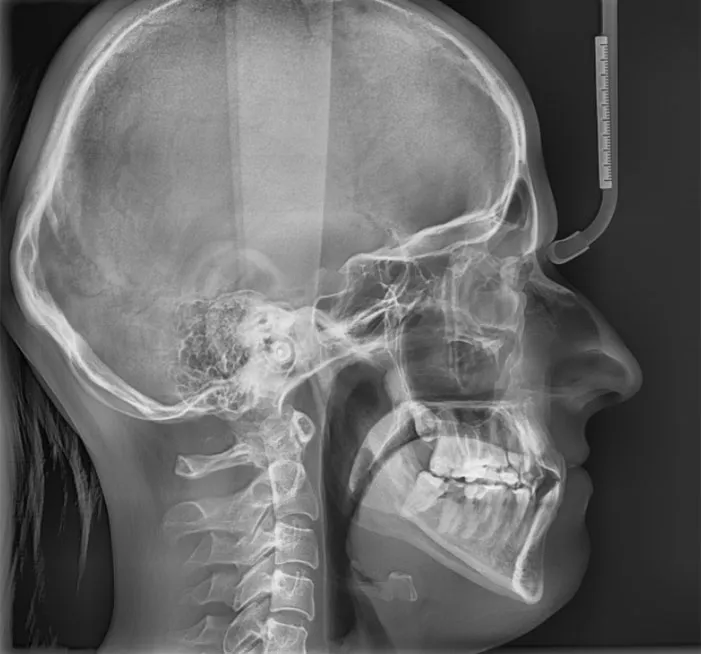

- Zdjęcia RTG: Zazwyczaj wykonuje się zdjęcie pantomograficzne (przeglądowe) i cefalometryczne (boczne), które pozwalają ocenić struktury kostne i położenie zębów. Ich analiza również jest wliczona w ten koszt. Razem to około 100 - 300 zł.